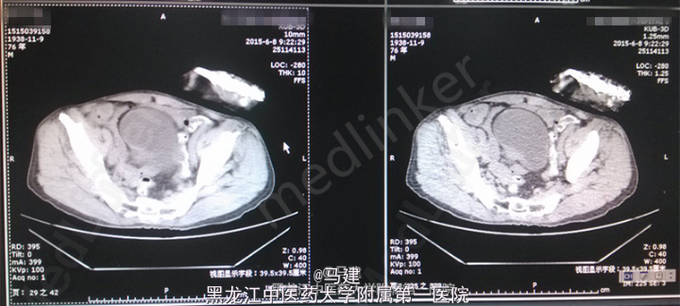

查体:T:36.2℃,P:64次/分,R:20次/分(规则),BP:138/83mmHg。神志清,精神可,全身浅表淋巴结无肿大,心肺腹未及明显异常,脊柱四肢活动自如。 专科情况:双肾区无明显压痛及叩击痛,输尿管行走区域正常,无压痛,膀胱叩诊呈浊音,无压痛,阴茎发育正常,无包茎或包皮过长,尿道外口正常,无狭窄、炎症分泌物,双侧阴囊对称,睾丸及附睾正常。前列腺直肠指检呈I°增大,中央沟存在,质地正常,无触痛,无结节。 入院后检查:血常规:RBC 4.29*10^12/L,Hb 123.0g/L,HCT 37.7%,WBC 3.55*10^9/L;尿常规:红细胞(+),红细胞计数 101.0/μl;尿培养:无细菌生长;三次尿脱落细胞学检查中一次偶见可疑Ca细胞;泌尿系CT示膀胱右侧壁见大小约23*42mm的软组织密度影。